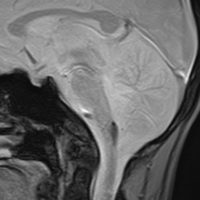

1歳5ヶ月で左小脳半球の髄芽腫になり手術と化学療法して,3歳になってから脳脊髄照射をしました。脳脊髄18グレイ,局所48グレイが入っています。18歳の学生の時のMRIで,左小脳萎縮がありますが普通の生活ができています。

18歳の時に突然,左上下肢の痺れと脱力が生じました。延髄下端から脊髄に小さな出血があります。様子を見ていたら症状はよくなりました。

その後数日の間に,小さな出血を繰り返して,嚥下障害,しゃっくり,頭痛,四肢のしびれなどが出ました。手術をしないで経過を見ました。

7年後のMRIです。延髄脊髄移行部(おそらくC1)に出血痕が残っています。放射線誘発海綿状血管腫といわれるものの画像所見ですが,ほんとのところは静脈閉塞によるうっ血症状と鬱血性の出血といわれています。

症状はすべて良くなりました。今は学校を卒業して,元気に働いています。